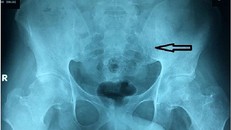

Sáng 17/8, bác sĩ (BS) Huỳnh Thị Tố Khanh, khoa Cơ xương khớp Bệnh viện (BV) Nhân dân 115 TP.HCM, cho biết BV vừa điều trị thành công viêm cột sống dính khớp cho bệnh nhân trẻ tuổi.